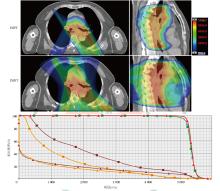

Objective To explore the dosimetric characteristics of proton radiotherapy plan and photon radiotherapy plan for esophageal cancer. Methods Four patients who were admitted to Shandong Cancer Hospital and Institute from January 2024 to April 2024 with esophageal cancer (cervical, middle thoracic and total esophageal tube, as well as the lymphatic drainage areas involved) and required radiotherapy were selected as the research subjects. Intensity modulated proton therapy (IMPT) and intensity modulated radiation therapy (IMRT) plans were designed respectively based on the clinical target volume and the dose constraints for organs at risk (OARs). Dosimetric parameters, including conformity index (CI), homogeneity index (HI), gradient index (GI) for target coverage, as well as OARs dosimetric parameters were evaluated. The volume of additional dose deposition in the body was compared by assessing regions receiving 10%, 30%, and 50% of the prescription dose. Results For all four cases, IMPT plans yielded lower HI values (0.12, 0.10, 0.06, and 0.08) than IMRT plans (0.15, 0.13, 0.10, and 0.11), and the GI values of IMPT plans (3.11, 3.21, 2.43, and 2.72) was lower than IMRT plans (4.52, 5.14, 3.09, and 3.92). Moreover, the CI of the IMPT plans (0.59, 0.60, 0.77, and 0.72) was inferior to IMRT plans (0.81, 0.77, 0.91, and 0.85). Compared with the IMRT plans, in the whole lung dose indicators of the IMPT plans for the 4 patients, V5 decreased by 34.1%, 55.0%, 79.7% and 60.3%, respectively; V20 decreased by 48.3%, 43.9%, 65.8% and 40.8%, respectively, and Dmean decreased by 43.4%, 57.2%, 76.2% and 45.4%, respectively. V30 of the heart decreased by 36.2%, 45.3%, 40.1% and 52.4%, respectively, and Dmean of heart decreased by 96.6%, 57.9%, 58.5% and 55.3%, respectively. For the middle and lower thoracic target area, the liver was significantly protected in the IMPT plan (Dmean decreased by 76.0% compared with the IMRT plan). In terms of the additional dose deposition in the patient's body, IMPT plans reduced the volumes receiving 10%, 30% and 50% of the prescription dose by 45.0%-61.4%, 41.2%- 61.8% and 34.8%-61.6%, respectively, compared with the IMRT plans. Conclusions By comparing the dosimetric parameters of IMPT and IMRT plans for 4 cases of esophageal cancer, the IMPT plans have advantages in reducing the doses to lung tissue, heart, and liver, and can also reduce additional dose deposition in the patient's body.